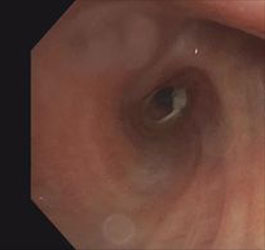

Bronchoscopy : Black Hole sign